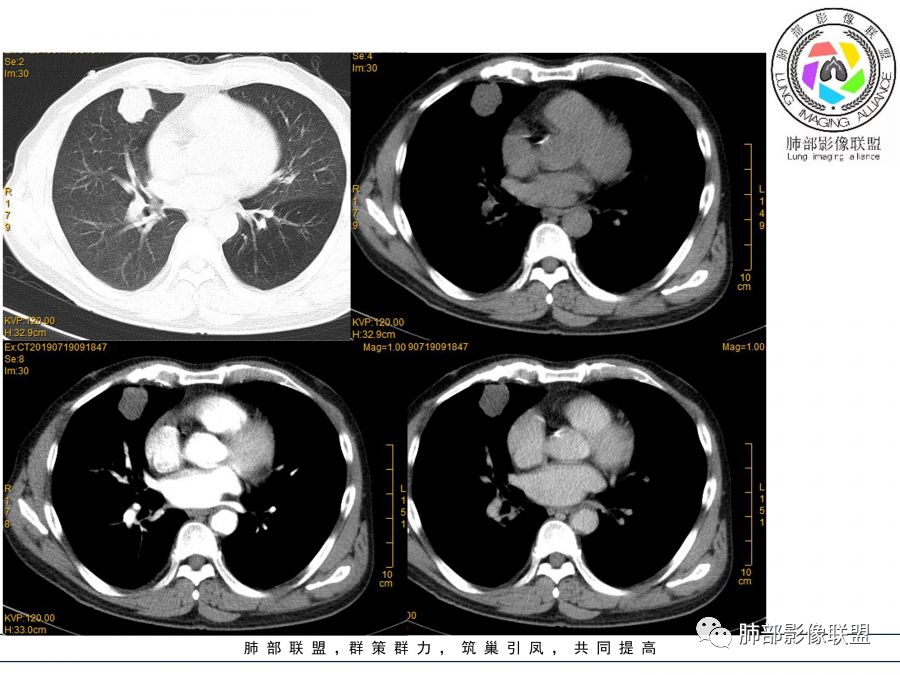

晨读病例  患者老年男性,因腰腹部疼痛3周,排尿困难1周入院。查尿常规及C反应蛋白提示泌尿系感染。肿瘤标志物NSE、细胞角蛋白19片断稍升高。胸部CT:右肺中叶内侧段类圆形肿块影,浅分叶,部分层面见深分叶,胸膜牵拉及支气管截断征象,边界清,密度低,无强化,且垮叶裂。综合考虑恶性病变,类癌及小细胞可能性大,鉴别囊肿等良性病变肺囊肿。

1.右肺中叶孤立不规则块影,浅分叶,未见液化或钙化,未见毛刺,未见脐凹,未见明显胸膜牵拉。

2.近肺门侧隐约见支气管截止。

3.外侧可见血管进入,病灶局部轻度强化。

上述均不符合光滑类圆形的支气管肺囊肿,也不符合典型的类癌,切不可先入为主。也不符合转移瘤。

4.肺门纵隔未见增大淋巴结。如此体量的肺块,没有增大淋巴结,不符合小细胞肺癌的生物学行为。

5.未见卫星灶,未见支气管增厚,结核也缺少支持点。

综上,应当鉴别的主要为肺鳞癌及结核灶